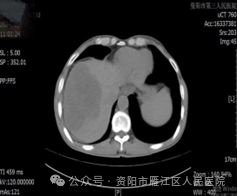

近日,56岁的李大叔因“右上腹疼痛20+天”入住我院。入院后查腹部增强CT:肝脏内结节、团块状稍低密度影,考虑肿瘤性病变。遂请超声科会诊, 腹部普通肝脏彩超提示:肝右叶实性占位,考虑肿瘤性病变可能。

超声造影:肝右叶实性占位性病变,考虑肝细胞Ca可能性大。